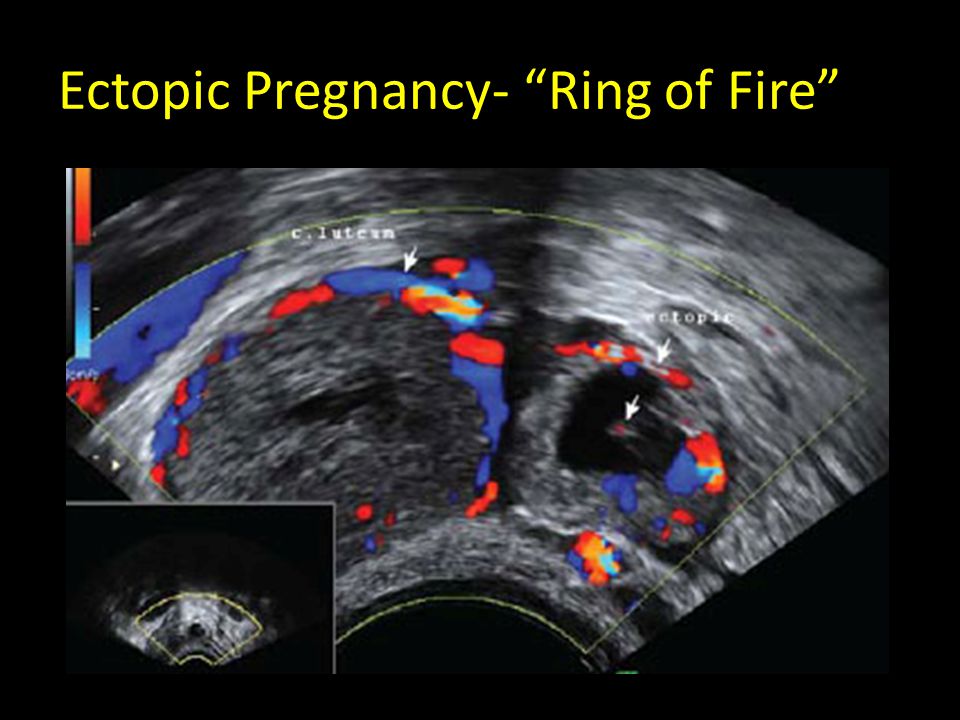

This is defined as peripheral hypervascularity of a hyperechoic ring surrounding an extrauterine gestation sac. We believe in creating a world in which all mothers are thriving. You may feel like you’ve already done so much work, but you may have a while yet to go. 7 things you can do to avoid the ring of fire during birth. Only.

You may feel like you’ve already done so much work, but you may have a while yet to go. The ring of fire sign, also known as ring of vascularity, signifies a hypervascular lesion with peripheral vascularity on colour or pulsed doppler examination of the adnexa due to low impedance high diastolic flow 1. 13 august 2020 broadridge financial solutions.

After i heard that i'm debating on drugs or not This is defined as peripheral hypervascularity of a hyperechoic ring surrounding an extrauterine gestation sac. Lol i am expecting my 3rd and i know i want the dope! The ring of fire sign, also known as ring of vascularity, signifies a hypervascular lesion with peripheral vascularity on colour or pulsed.

Emphasis is placed on how to exclude the diagnosis of ectopic pregnancy. The tubal ring sign is an adnexal thick echogenic trophoblastic tissue surrounding a central hypoechoicity. I had this wit both both first and second. You may feel like you’ve already done so much work, but you may have a while yet to go. The serum beta hcg level.